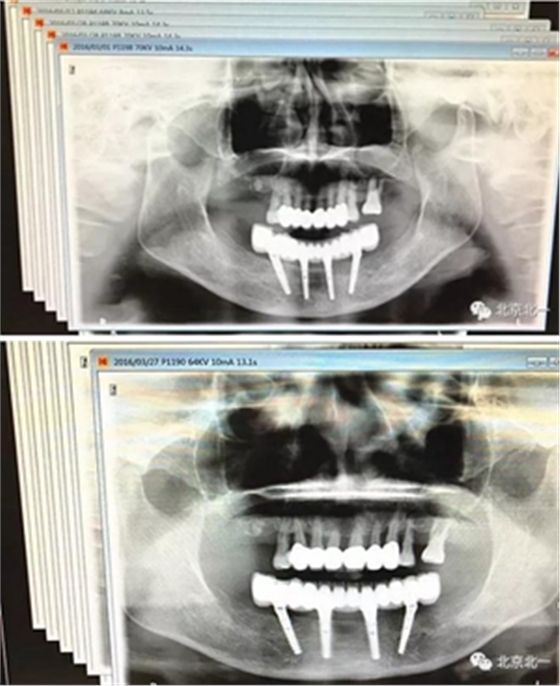

圖二十二:2015年到2016年復(fù)查時X片 ,有圖有真相

沒有假貨,貨真價實,完成三年復(fù)查。

圖二十三:有圖有真相。